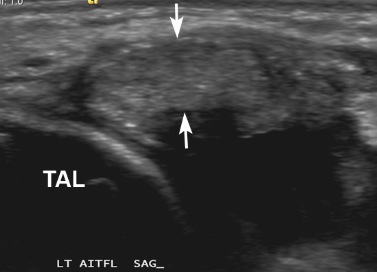

Figure 1 for case AITFL Desmitis

Figure 1

39 with on-going anterolateral ankle pain 9 months after syndesmosis injury. Pain, tenderness and swelling all localised to the AITFL. US shows AITFL Desmitis with tender, diffusely swollen and mildly hyperaemic ligament (arrows).

AITFL Desmitis